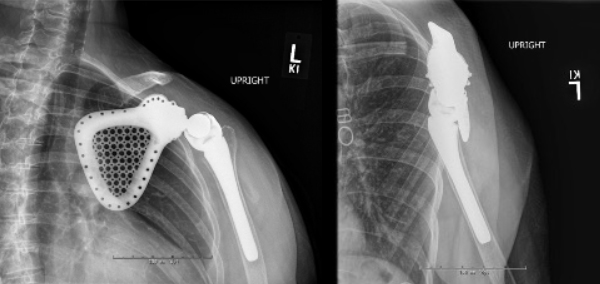

Figure 2: Post-operative radiographs showing left scapular resection with reverse shoulder arthroplasty.